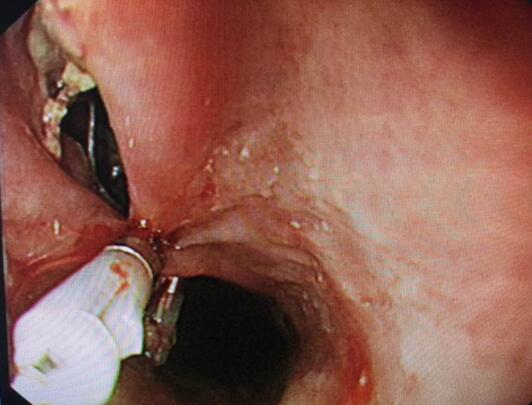

内镜中心王莹副主任考虑到患者病情复杂且高龄,不具备急诊外科手术条件,在确保患者安全情况下行内镜下异物钳取术、钛夹封闭损伤治疗。术中观察到梭形枣核嵌顿于患者食管上端,一侧食管壁可见纵形全层伤口,损伤非常严重。王主任克服困难,以她熟练的操作最终将异物顺利取出。

食道损伤

钛夹逐渐夹闭损伤